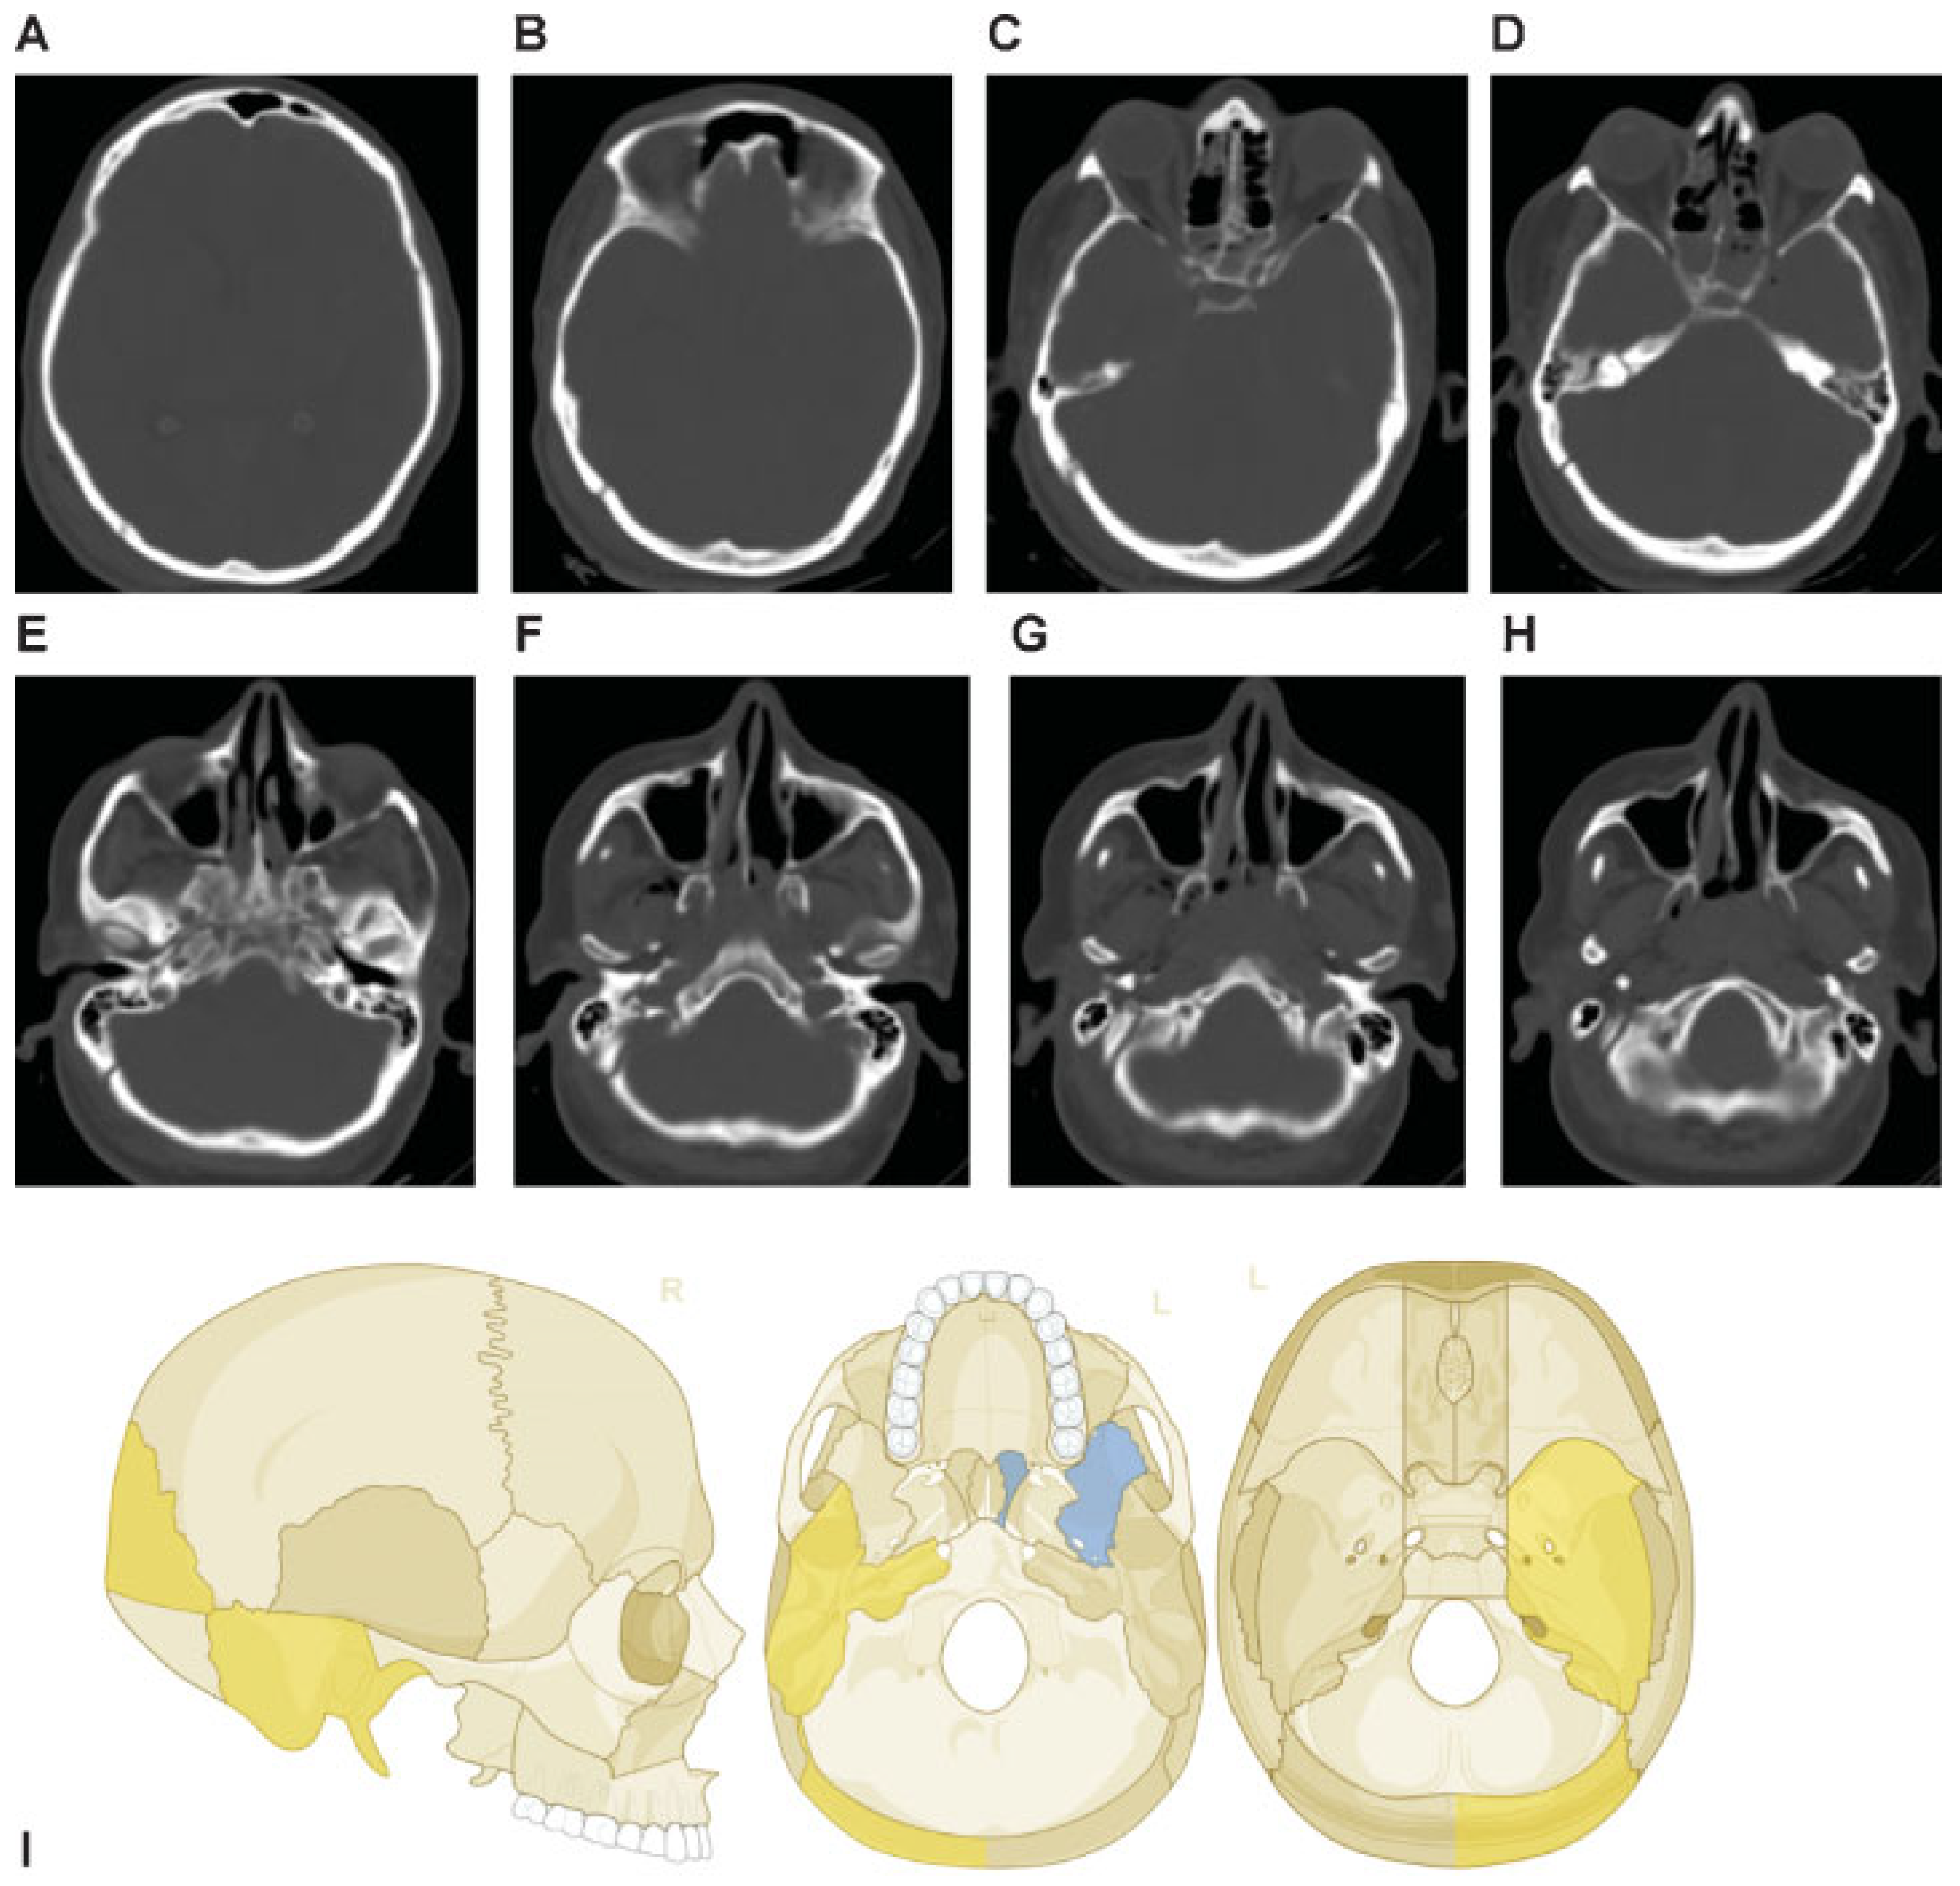

Fractures of the walls of the paranasal sinuses with the presence or the absence of opacification of the paranasal sinuses on CT imaging (i.e., blood or other fluids) are also documented. Illustrative examples are presented in Figure 3 and Figure 4A.

Figure 3. Examples of fractures and definitions. (A) Depressed fracture (displaced toward the brain) of the parietal bone. (B) Multiple fractures, depressed on the right frontal bone, displaced on the left frontal bone, with involvement and opacification of the frontal sinus bilaterally. (C) Transverse fracture line through the right petrous bone, another fracture line through the right apex petrosis, opacification of the left mastoid with fracture at the rostral rim. (D) Transverse maximum intensity projection (MIP) – reconstruction of the skull base with fragmented fracture of the right middle skull base fossa. (E): Nonfragmented fracture of the left parietal bone. (F) Curved MIP—reconstruction of the occipital bones with fragmented fracture, displaced but not depressed.